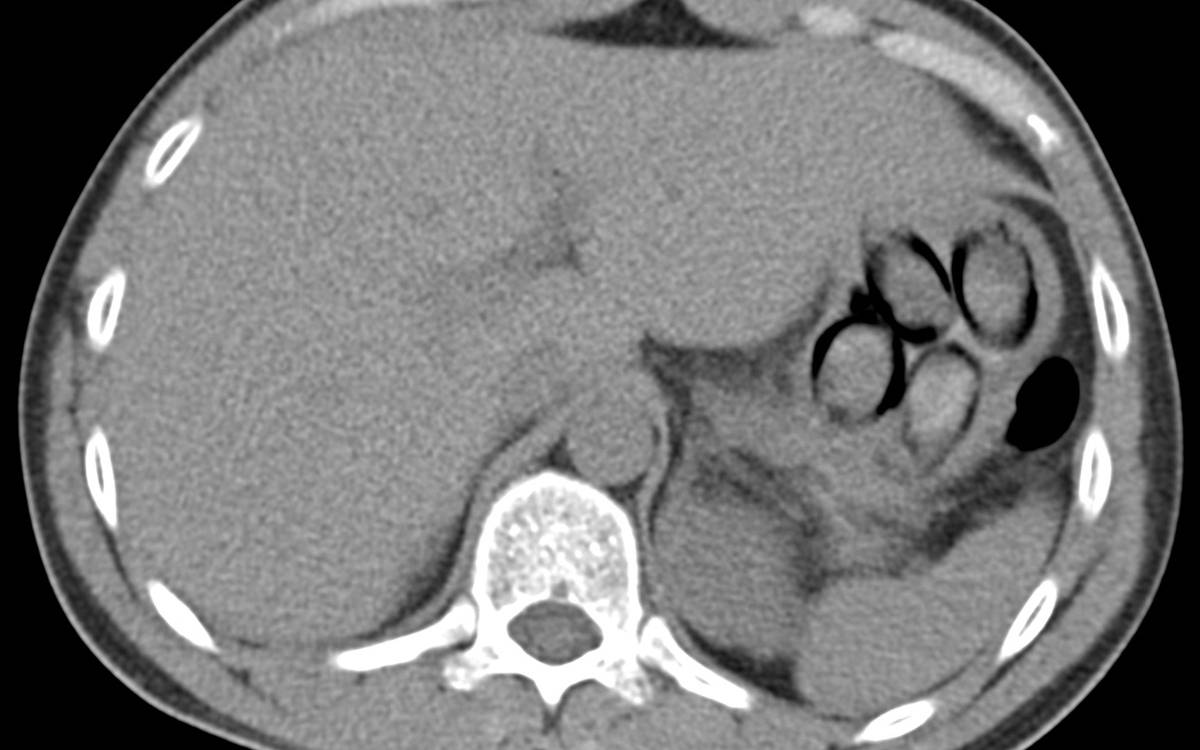

Er kam aus Den Haag und wollte nach Frankfurt. Die Zollbeamten machten einen sogenannten Wisch-Test an den Handinnenflächen des Mannes, der Test reagierte auf Kokain. Eine Röntgenaufnahme in einem nahegelegenen Krankenhaus bestätigte die Vermutung der Beamten. Der Mann hatte Beutelchen mit Kokain in seinem Magen. Insgesamt waren es sieben davon, mit über einhundert Gramm Koks.